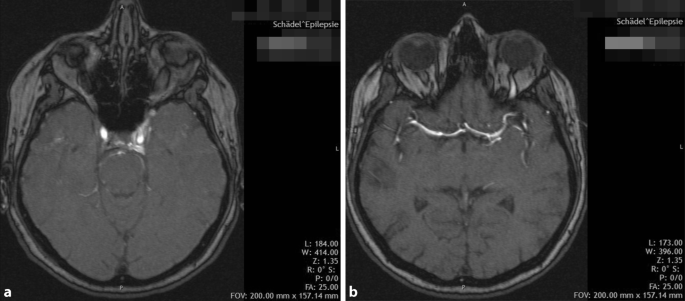

Carotis sinus cavernosus fistel. Ihren Ästen und Sinus cavernosus. Direkte Shuntverbindung zwischen der Arteria carotis interna und des Sinus cavernosus. A Angiographie der Arteria carotis communis in seitlichem Strahlengang.

Eine spezielle Komplikation nach einem Schädel-Hirn-Trauma insbesondere nach Schädelbasisverletzung stellt die Carotis-sinus-cavernosus-Fistel dar. Carotis mit vollständiger Rückbildung der Symptome in einem Fall. Typisch sind gestaute episklerale Venen bei wechselnd ausgeprägter Protrusio bulbi.

Carotis interna im Sinus cavernosus verletzt fließt das Blut der Arterie in den venösen Sinus. Traumatisch frontobasale Schädelbasisfraktur Aneurysmaruptur A.

Es resultiert ein Anstieg des Venendrucks im Sinus und der in ihn drainierenden Strukturen.